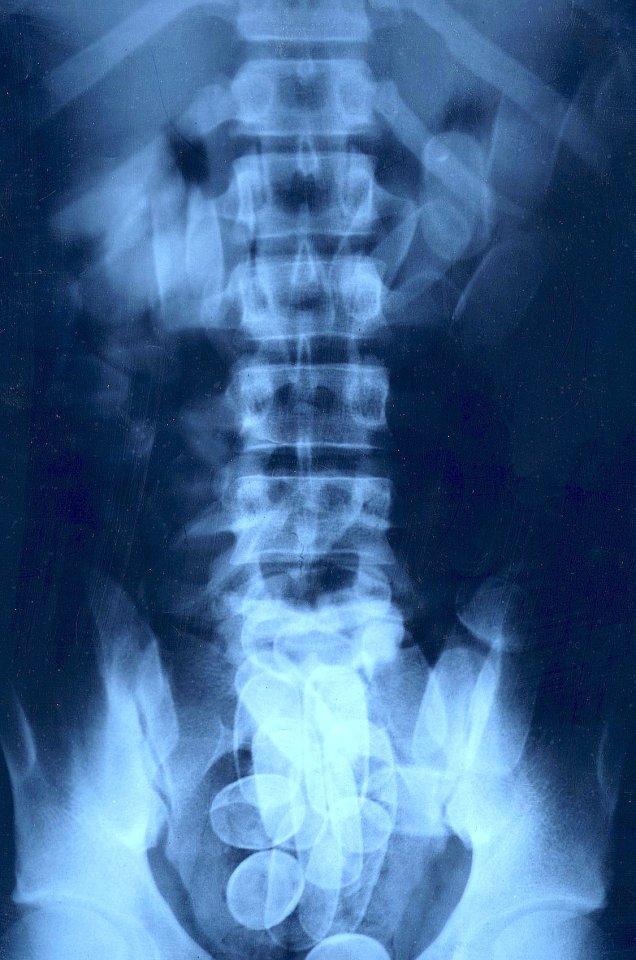

Hier sind oft Körperschmuggler unterwegs, die Kokain, verpackt in Cocktailwürstchen-große Latex-Fingerlinge, in Magen und Darm transportieren. Es ist wohl einer der gefährlichsten Jobs im internationalen Rauschgifthandel: Platzen diese „Bolitas“ im Körper, kann so ein Kurier an Organversagen sterben. Entkommen sie dagegen den gesundheitlichen Risiken und am Ende auch dem Zoll, zahlen ihnen die Hintermänner einen Transportlohn bis zu 5000 Dollar, für die meist bitterarmen „Bodypacker“ ein Vermögen.

Wird bei der Kontrolle ein Bodypacker gestellt, muss er sich auf einer Spezialtoilette erleichtern, das ausgeschiedene Material wird als Beweis eingesammelt. Nach manchen Flügen wurden sieben Körperschmuggler unter den Passagieren entdeckt. Etliche mussten sofort in die nächste Klinik: Notoperation!

Die nordrhein-westfälische Landeshauptstadt ist nicht erst seit heute ein Schwerpunkt dieser Spielart des Drogenhandels. Schon 2012 gingen hier 85 der bundesweit 130 ertappten Körperschmuggler ins Netz. 61 wurden im letzten Jahr enttarnt, sie hatten 3354 Koks-Päckchen verschluckt – im Schnitt hatte jeder 55 „Politas“ im Bauch. Zwölf Prozent der deutschen Kokain-Sicherstellungen überhaupt gehen aufs Konto der Düsseldorfer Flughafen-Fahnder.